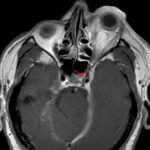

Orbital compartment syndrome (OCS) is an ophthalmologic emergency due to an acute rise in intra-orbital pressure and can result in permanent vision loss, oftentimes requiring emergent surgical decompression. Orbital compartment syndrome most commonly occurs due to recent trauma and is often easily diagnosed by history and physical exam. However, there are other causes of OCS where a more subacute/chronic rise in pressure can lead to an atypical presentation. This is a case report of a 48-year-old male who presented with left eye pain and swelling for the past 6 months. The patient had seen two ophthalmologists prior to his emergency department (ED) presentation who had prescribed him an antibiotic ointment, oral steroids, and steroid eye drops. The physical exam in the ED was concerning for increased intra-ocular pressure (IOP) and decreased vision. Ophthalmology was consulted and requested magnetic resonance angiography (MRA) to assess a vascular etiology given tortuous retinal vasculature. Emergent surgical decompression was deferred due to chronicity of symptoms, and patient was started on dorzolamide/timolol and brimonidine eye drops as well as intravenous (IV) acetazolamide with subsequent improvement in IOP. Imaging revealed a left carotid-cavernous sinus fistula (CCF), and the patient was admitted to neurosurgery. Patient successfully had an embolization with subsequent normalization of IOP and improvement of symptoms. This case is a good example of how non-traumatic causes of OCS can lead to misdiagnosis and how surgical decompression could potentially be deferred in subacute OCS.